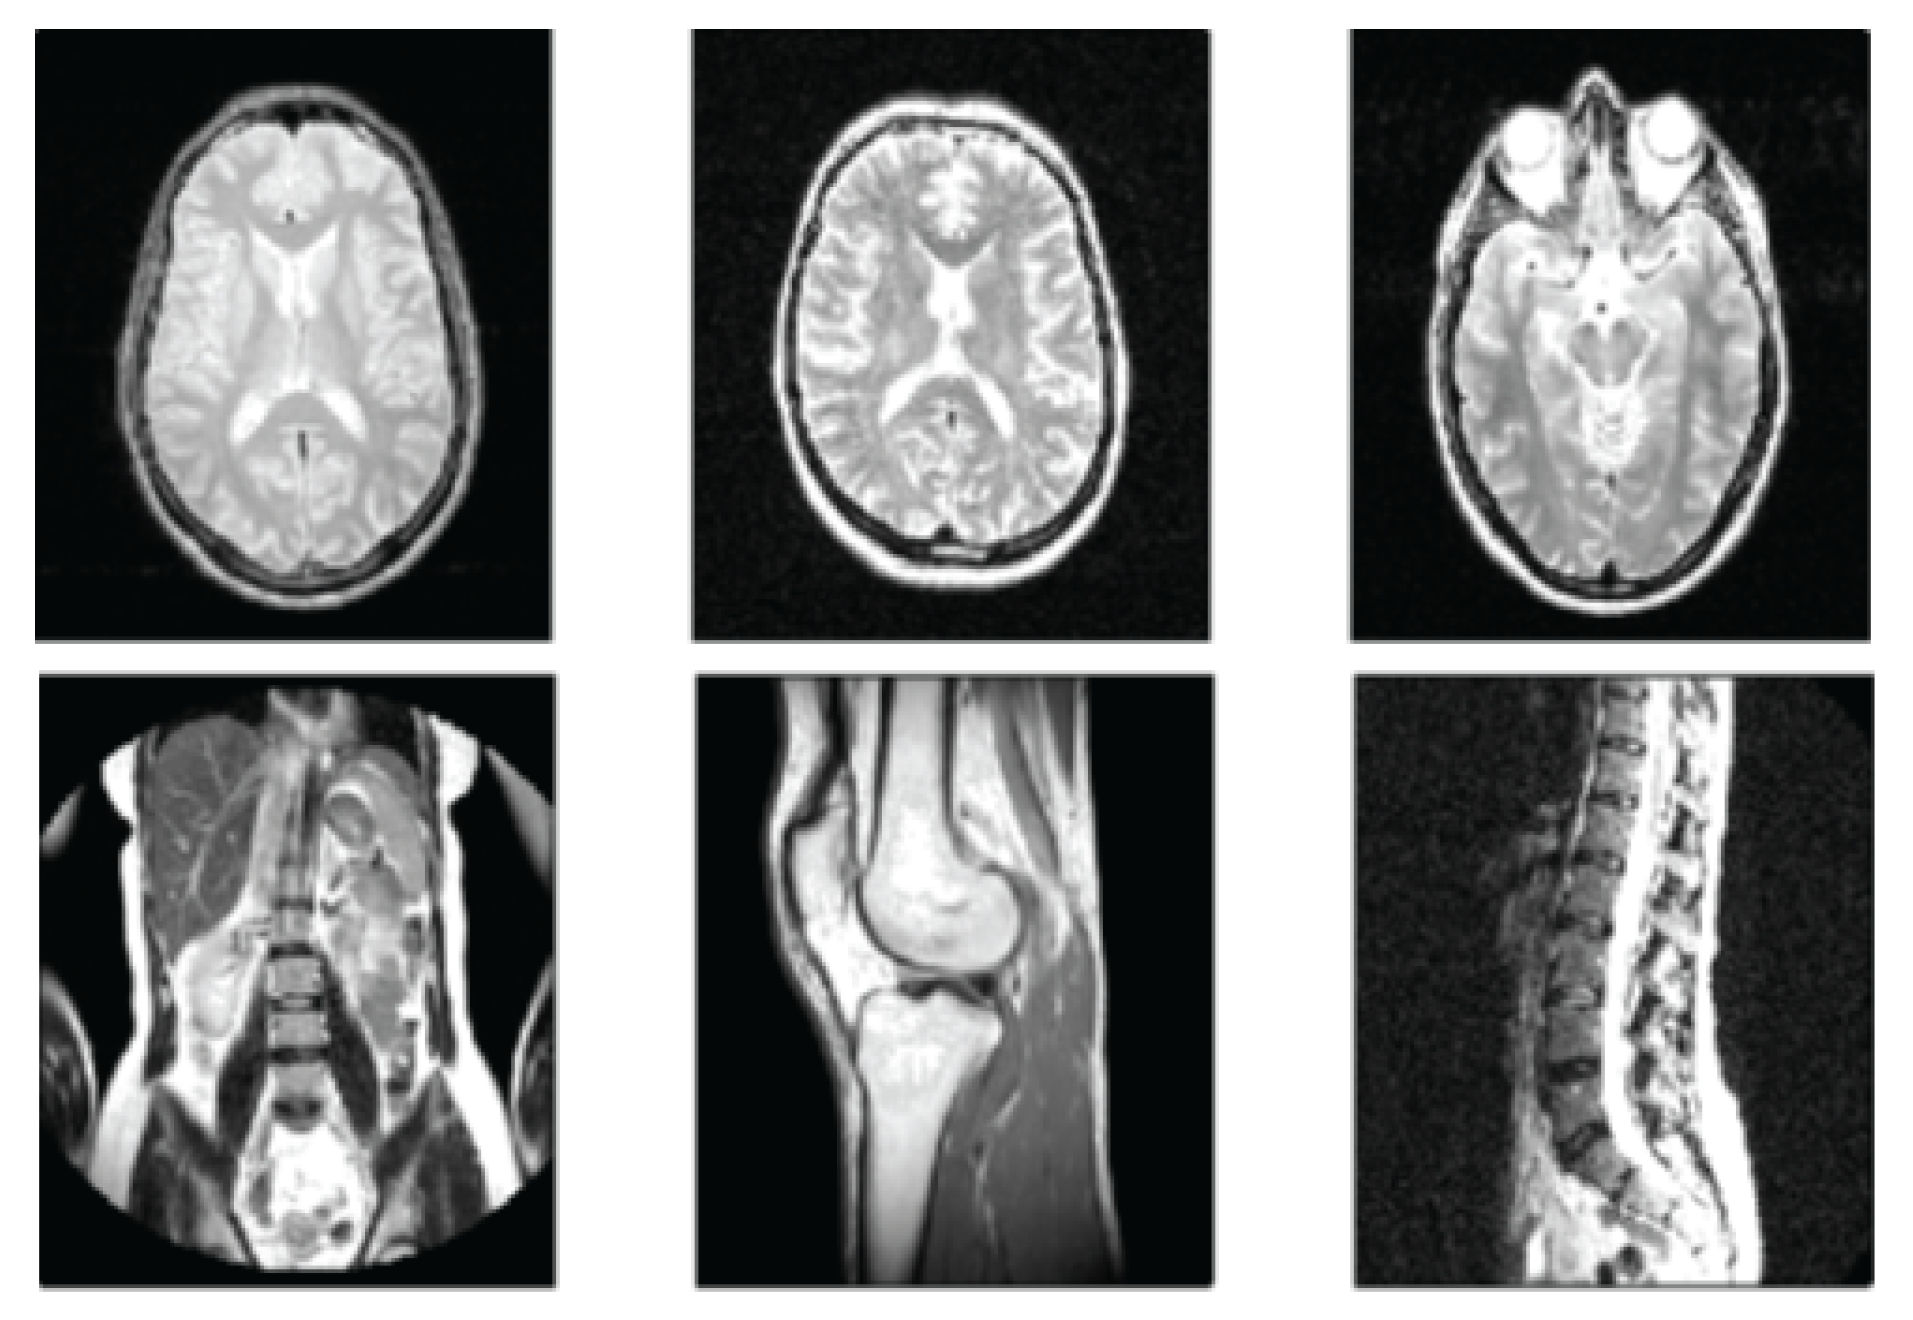

2.3. Magnetic Resonance Imaging (MRI)